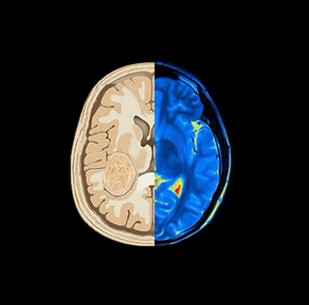

The instantaneous concentration of contrast material within each voxel is calculated by comparing the tissue attenuation at any time point with baseline images obtained before the arrival of the contrast bolus. Combining the measurements drawn from the several time points produces a concentration-versus-time curve (C1) for each voxel. Then a mathematical analysis of C1 for each voxel, generates a number of important parameters of hemodynamic performance, such as CBF, CBV, MTT, and the time-to-peak tissue response.

Now that we have a basic understanding of image acquisition in brain perfusion CT, we need to look at 4 essential hemodynamic parameters including: CBV, CBF, MTT and Tmax.

Cerebral Blood Volume (CBV)

The Cerebral Blood Volume CBV, is defined as the volume occupied by intravascular blood in any particular section of brain tissue. It is measured in units of milliliters of blood per 100 g of brain.

Cerebral Blood Flow (CBF)

Moving to the 2nd parameter in brain CT perfusion, the CBF is defined as the volume of blood passing through a given amount of brain tissue per unit of time, most commonly milliliters of blood per minute per 100g of brain tissue.

Mean Transit Time (MTT)

The third main parameter to take into consideration is the Mean Transit Time. MTT is measured in seconds and defined as the average amount of time it takes blood to transit within the blood vessels in a particular region of the brain. In brain imaging, maps of MTT are the most commonly used in clinical situations.